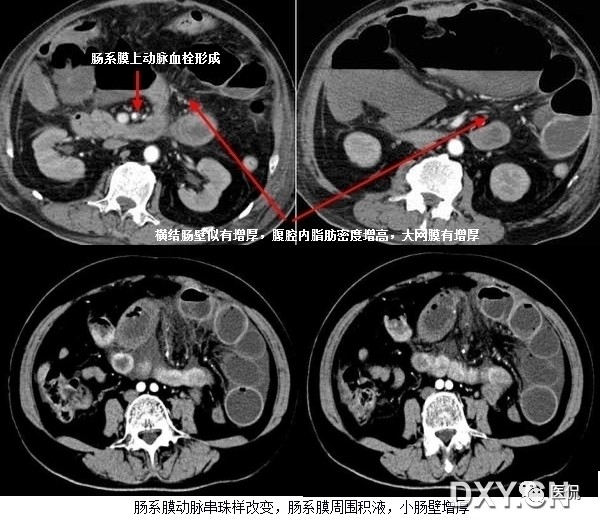

肠系膜脂肪受炎症细胞、液体(水肿、淋巴液和血液)、肿瘤浸润及纤维化的CT表现。当肠系膜被液体或细胞浸润时,其脂肪CT值增加到-40~ -60HU(肠系膜脂肪的CT值类似于皮下及腹膜后脂肪,约-100~-160hu,肠系膜血管常呈横行或断面显示。),动、静脉失去锐利边缘。根据浸润的性质和范围,肠系膜血管可部分或完全模糊,顺着脏层腹膜常能发现肠系膜疾病的线索,在周围脂肪衬托下,肠系膜病变显示更加清晰。

上两幅图:肠系膜上动脉栓塞

下两幅图:十二指肠扭转致肠壁增厚、肠系膜水肿

肠系膜水可由许多疾病引起,如低蛋白血症、肝硬化、肾病、心力衰竭、三尖瓣狭窄病变、缩窄性心包炎、门脉高压、门静脉血栓、肠系膜血管栓塞、血管炎、柏-查综合症、下腔静脉阻塞和外伤等,如肠系膜水肿是由全身性疾病引起,则有广泛的皮下水肿和覆水。CT扫描常由于身体近床侧的皮下组织内有新月状高密度影,代表增多的细胞外水分,肠系膜呈云雾状改变的范围从肠管的浆膜面直到肠系膜上动、静脉起始部的肠系膜根部;肝硬化由于低蛋白血症门脉高压常引起肠系膜水肿。肠系膜动、静脉血栓所引起的肠系膜水肿可呈局限性或弥漫性,发现血管内栓子或管腔缩小常可提示肠系膜血管栓塞,肠缺血的其他征象为节段性肠壁增厚,气肿性肠炎,当出现坏死时可有小静脉分支内集气。